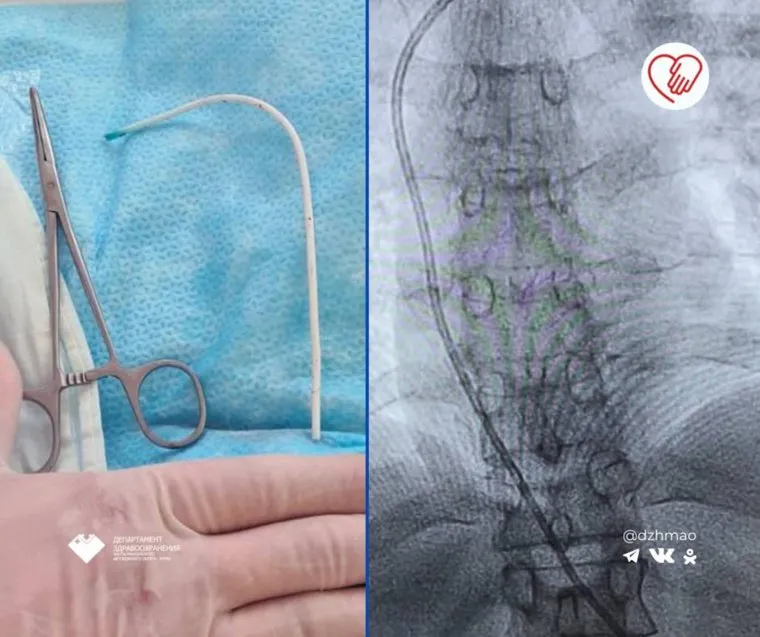

Хирурги окружной больницы Нижневартовска (ХМАО) извлекли из сердца пациентки 12-сантиметровый обломок венозного катетера. Информацию об этом сообщили в telegram-канале департамента здравоохранения Югры.

«В приемный покой окружной больницы Нижневартовска поступила пациентка с миграцией венозной портсистемы. Во время обследования медики выявили протяженный участок (12 см) отломившегося катетера, который переместился в правое предсердие», — говорится в публикации.

Ситуация была критической — наличие постороннего предмета в предсердии могло привести к смертельным последствиям: образованию тромбов и остановке сердца. Хирурги ввели инструмент с петлей в яремную вену, аккуратно захватили обломок катетера и извлекли его. Операция прошла успешно.

12-сантиметровый катетер, который медики извлекли из сердца пациентки